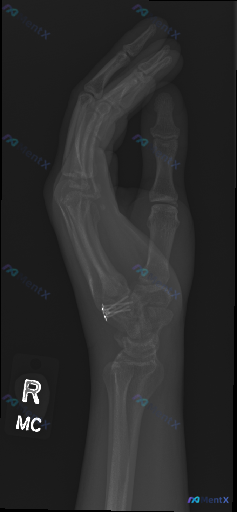

整理到一张影像资料和对应的分析背景,想和大家讨论读片思路。 基本情况 - 检查:右侧手部侧位X光片 - 已知背景:腕骨区域(舟骨/大多角骨连接处)可见多枚高密度金属内固定物,提示曾行手术治疗 影像主要表现(整理自描述) 1. 骨骼:第II-V掌骨及指骨皮质连续,未见明确新发骨折线;腕部内固定处骨结构...